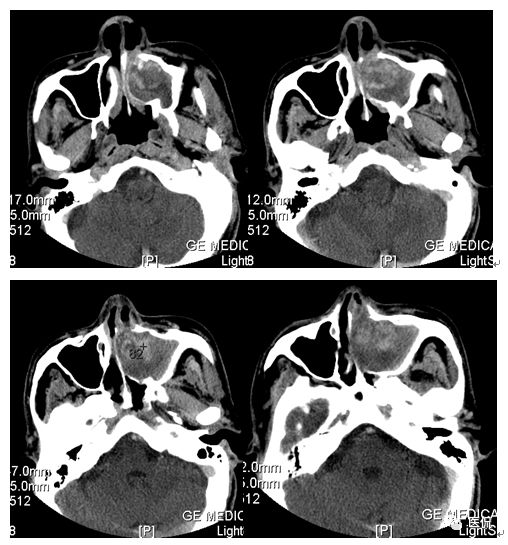

男,73岁,以“左鼻塞流脓涕4个月”为主诉入院。诉缘于4个月前无明显诱因出现左鼻塞、流脓涕,伴左侧鼻腔嗅觉减退,偶有出血(2-3次)。鼻内窥镜示:鼻腔粘膜弥漫性充血肿胀,左侧鼻腔见一新生物完全充满其内,无空隙,表面附着清粘涕及少许血迹,右侧下鼻甲肥大,右侧中下鼻道狭窄,右侧鼻咽部光滑,右侧咽隐窝存在。

CT平扫及增强示:左侧上颌窦及鼻腔可见软组织密度影,呈膨胀性生长,周围骨质压迫性吸收破坏,累及左眶,病灶密度不均匀,周边区可见点状钙化,增动脉期轻度强化,局部见小灶性稍高密度区,静脉期病灶内见不均匀明显强化,CT值最高达117HU,延迟期强化范围有所增大。

本例病灶较大,周围骨质可见吸收破坏,并累及眼眶,病灶内少量钙化,增强扫描具有一定特征性,表现为动脉期轻度强化,局部见小灶性稍高密度区,静脉期病灶局部呈明显强化,CT值最高达117HU,延迟期强化范围有所增大,呈延迟渐进性强化的特点,推测为病灶内出血所致。